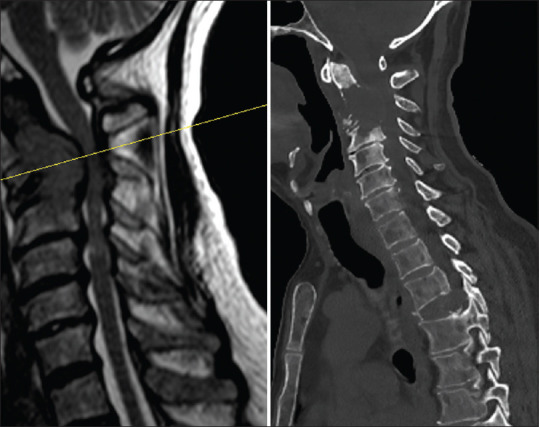

枕颈交界处(OCJ)是一个复杂的解剖区域,对保护下脑干、上脊髓和下颅神经至关重要。该区域的不稳定性可导致慢性疼痛、神经功能缺损或死亡等严重后果。目前已开发出多种用于稳定 OCJ 的手术技术,尤其是使用枕骨髁螺钉,这些技术在提供稳定性和保持颈部旋转方面已显示出良好的前景。本文介绍了两例因C2椎体转移性受累而导致的OCJ不稳定病例,这两例病例均采用枕骨髁螺钉固定术成功治愈。第一例患者是一名 22 岁的女性,患有尤文肉瘤转移;第二例患者是一名 62 岁的男性,患有多发性骨髓瘤。两名患者术后的神经功能和颈椎稳定性均有明显改善,并可观察到穴位重塑。我们的研究结果表明,枕骨髁螺钉固定术不仅可行,而且能有效治疗转移性疾病导致的 OCJ 不稳定。详细的术前评估和使用先进的术中成像技术(如 O 型臂和神经导航)对于最大限度地提高安全性和确保最佳治疗效果至关重要。这项研究强调了枕骨髁螺钉固定术作为一种主要手术方法在适当病例中稳定 OCJ 的潜力。

The occipitocervical junction (OCJ) is a complex anatomical region crucial for protecting the lower brain stem, upper spinal cord, and lower cranial nerves. Instability in this area can lead to severe outcomes such as chronic pain, neurological deficits, or death. Various surgical techniques have been developed for OCJ stabilization, particularly using occipital condyle screws, which have shown promise in providing stability and preserving neck rotation. This article presents two cases of OCJ instability caused by metastatic involvement of the C2 vertebra, managed successfully with occipital condyle screw fixation. The first case involved a 22-year-old female with Ewing sarcoma metastasis, and the second case involved a 62-year-old male with multiple myeloma. Both patients exhibited significant improvements in neurological function and cervical stability postoperatively, with observable den remodeling. Our findings suggest that occipital condyle screw fixation is not only feasible but also effective in managing OCJ instability due to metastatic disease. Detailed preoperative evaluation and the use of advanced intraoperative imaging technologies, such as the O-arm and neuronavigation, are essential for maximizing safety and ensuring optimal outcomes. This study underscores the potential of occipital condyle screw fixation as a primary surgical method for stabilizing the OCJ in appropriate cases.